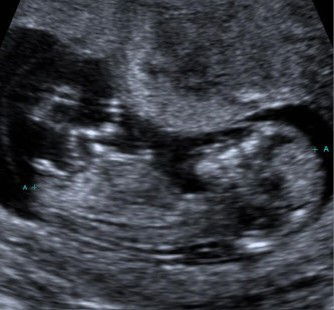

Guess the gender!

Is this a girl or boy? Hubby and I have differing opinions 😆 What do you all think?

I think your baby is a boy cause i see his scrotum ☺️your baby open his legs..so nice..Congrats mummy!

Looks like a boy! The 2nd pic looks very different from mine (girl) ☺️

guessing boy based on 2nd pic! :)